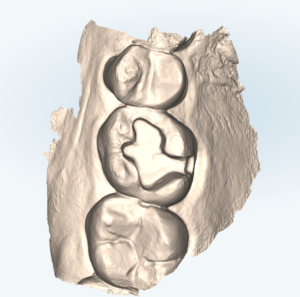

セラミックの詰め物に適した形態に修正した歯

セラミックの詰め物に適した形態に修正した歯